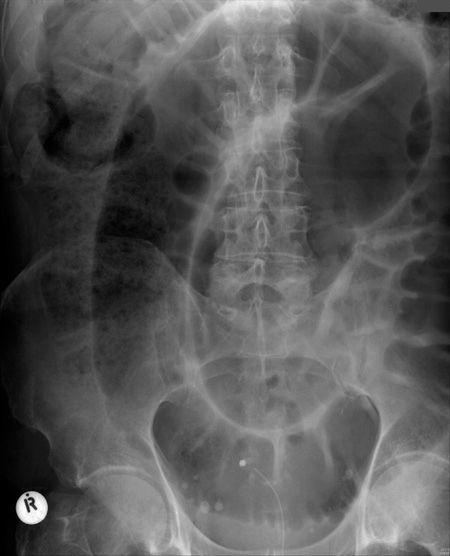

Radiology Masterclass@RadMasterclass·

ABDOMINAL X-RAY 45: Abdominal pain and constipation. What is the radiological diagnosis? Answer bit.ly/3PNyx5k